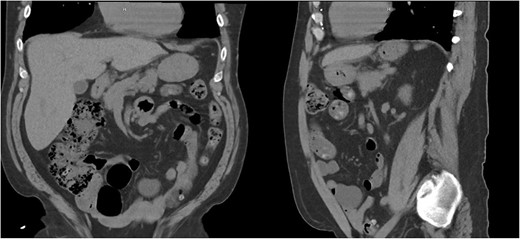

Approximately ten years prior, he had undergone coronary artery bypass surgery (CABG) with a xiphoidectomy. His symptoms at the time of the CT were right upper quadrant pain and epigastric fullness. He was referred for outpatient surgical evaluation. Shortly after the initial surgical assessment, he presented to the emergency department with gastric outlet obstruction. An abdominal CT was performed, showing a right-sided type 4 anterior diaphragmatic hernia with herniation of the antrum and pylorus causing the obstruction (Fig. 2). A loop of the transverse colon was also herniated into the thorax but without colonic obstruction.

Right-sided type 4 anterior diaphragmatic hernia with antrum and pylorus herniation.